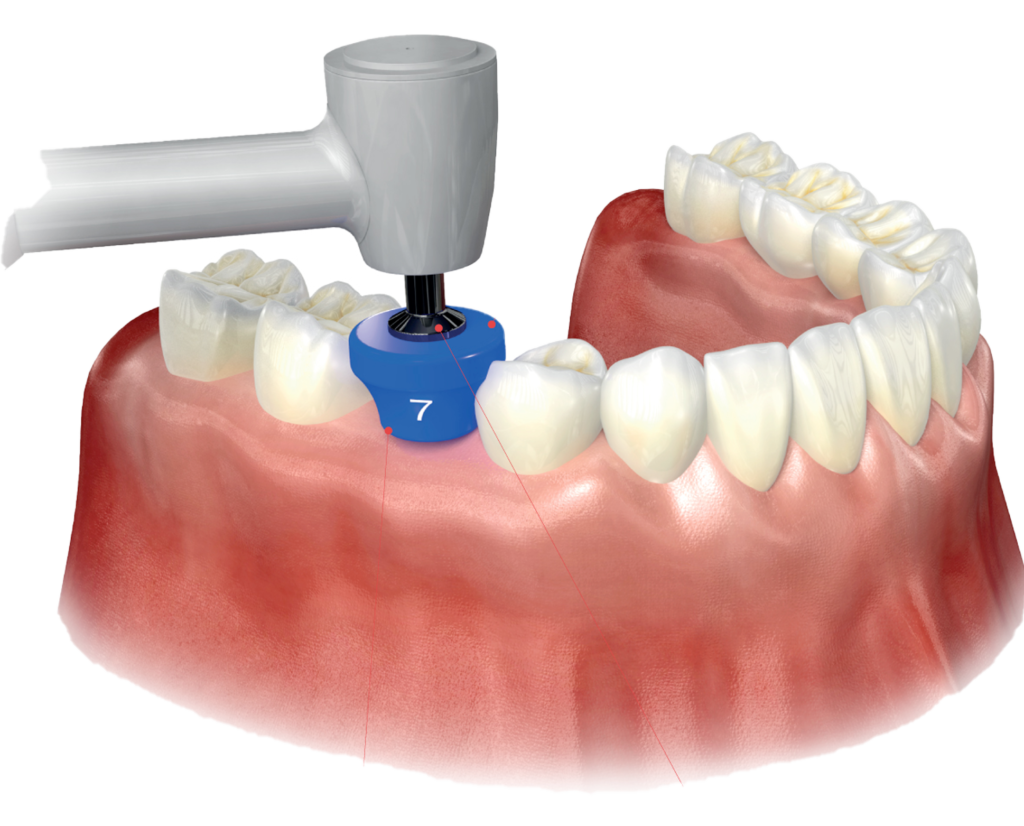

サージカルステントとは

インプラントを入れるドリルを正確にガイドします